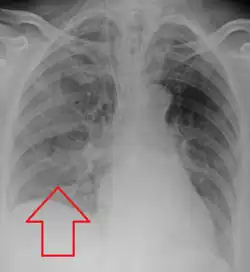

Aspiration pneumonia in a ventilated person with a central line and nasogastric tube

Aspiration pneumonia is typically diagnosed by a combination of clinical circumstances (people with risk factors for aspiration) and radiologic findings (an infiltrate in the proper location).[1] A chest x-ray is typically performed in cases where any pneumonia is suspected, including aspiration pneumonia.[18] Findings on chest x-ray supportive of aspiration pneumonia include localized consolidation depending on the patient's position when the aspiration occurred.[18] For example, people that are supine when they aspirate often develop consolidation in the right lower lobe of the lung.[18] Sputum cultures are not used for diagnosing aspiration pneumonia because of the high risk of contamination.[19] Clinical symptoms may also increase suspicion of aspiration pneumonia, including new difficulty breathing and fever after an aspiration event.[6] Likewise, physical exam findings such as altered breath sounds heard in the affected lung fields may also be suggestive of aspiration pneumonia.[6] Some cases of aspiration pneumonia are caused by aspiration of food particles or other particulate substances like pill fragments; these can be diagnosed by pathologists on lung biopsy specimens.[20]